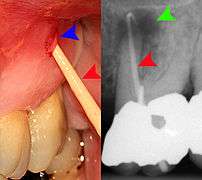

Decay (green) with apical abscess (blue)

Gutta-percha point indicating abscess origin

The periodontal ligament becomes inflamed and there may be pain when biting or tapping on the tooth. On an X-ray, bone resporption appears as a radiolucent area around the end of the root, although this does not manifest immediately.[9]:228 Acute apical periodontitis is characterized by well-localized, spontaneous, persistent, moderate to severe pain.[4]:125–135 The alveolar process may be tender to palpation over the roots. The tooth may be raised in the socket and feel more prominent than the adjacent teeth.[4]:125–135